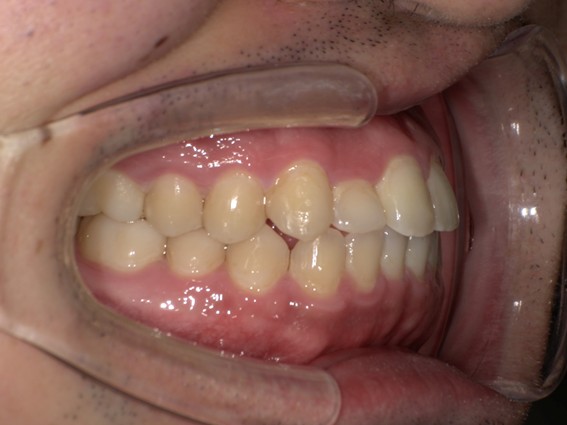

| 主訴 | 前歯が逆に噛んでいるところがある。歯のがたつき。 |

| 治療内容 | 表側ワイヤー矯正、4本抜歯を行いました。 |

| 治療費 | 880,000円+ダイレクトボンディング33,000円(税込) |

| 治療期間 | 30ヶ月 |

| 治療回数 | 30回 |

| 想定されたリスク | 歯根吸収、歯髄壊死、歯髄充血、歯肉退縮のリスクがありました。 |